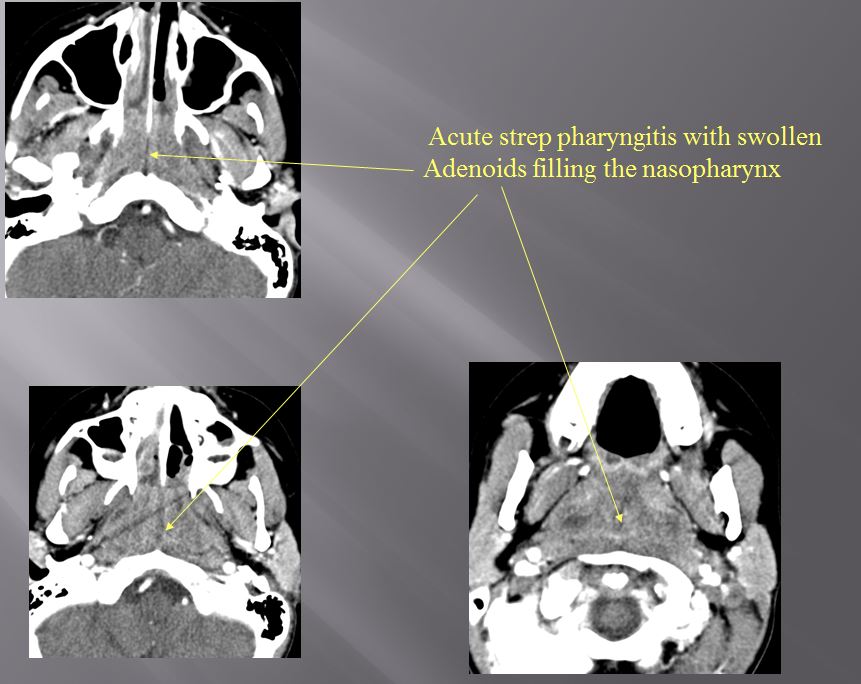

Nasopharynx

There is excessive enhancement or thickening of the mucosa or hypertrophy of the lymphoid tissue in the nasopharynx.

Oropharynx

There is excessive enhancement or thickening of the mucosa or hypertrophy of the palatine or lingual tonsillar tissue or the lymphoid tissue along the glossotonsillar sulci and posterior pharyngeal wall.